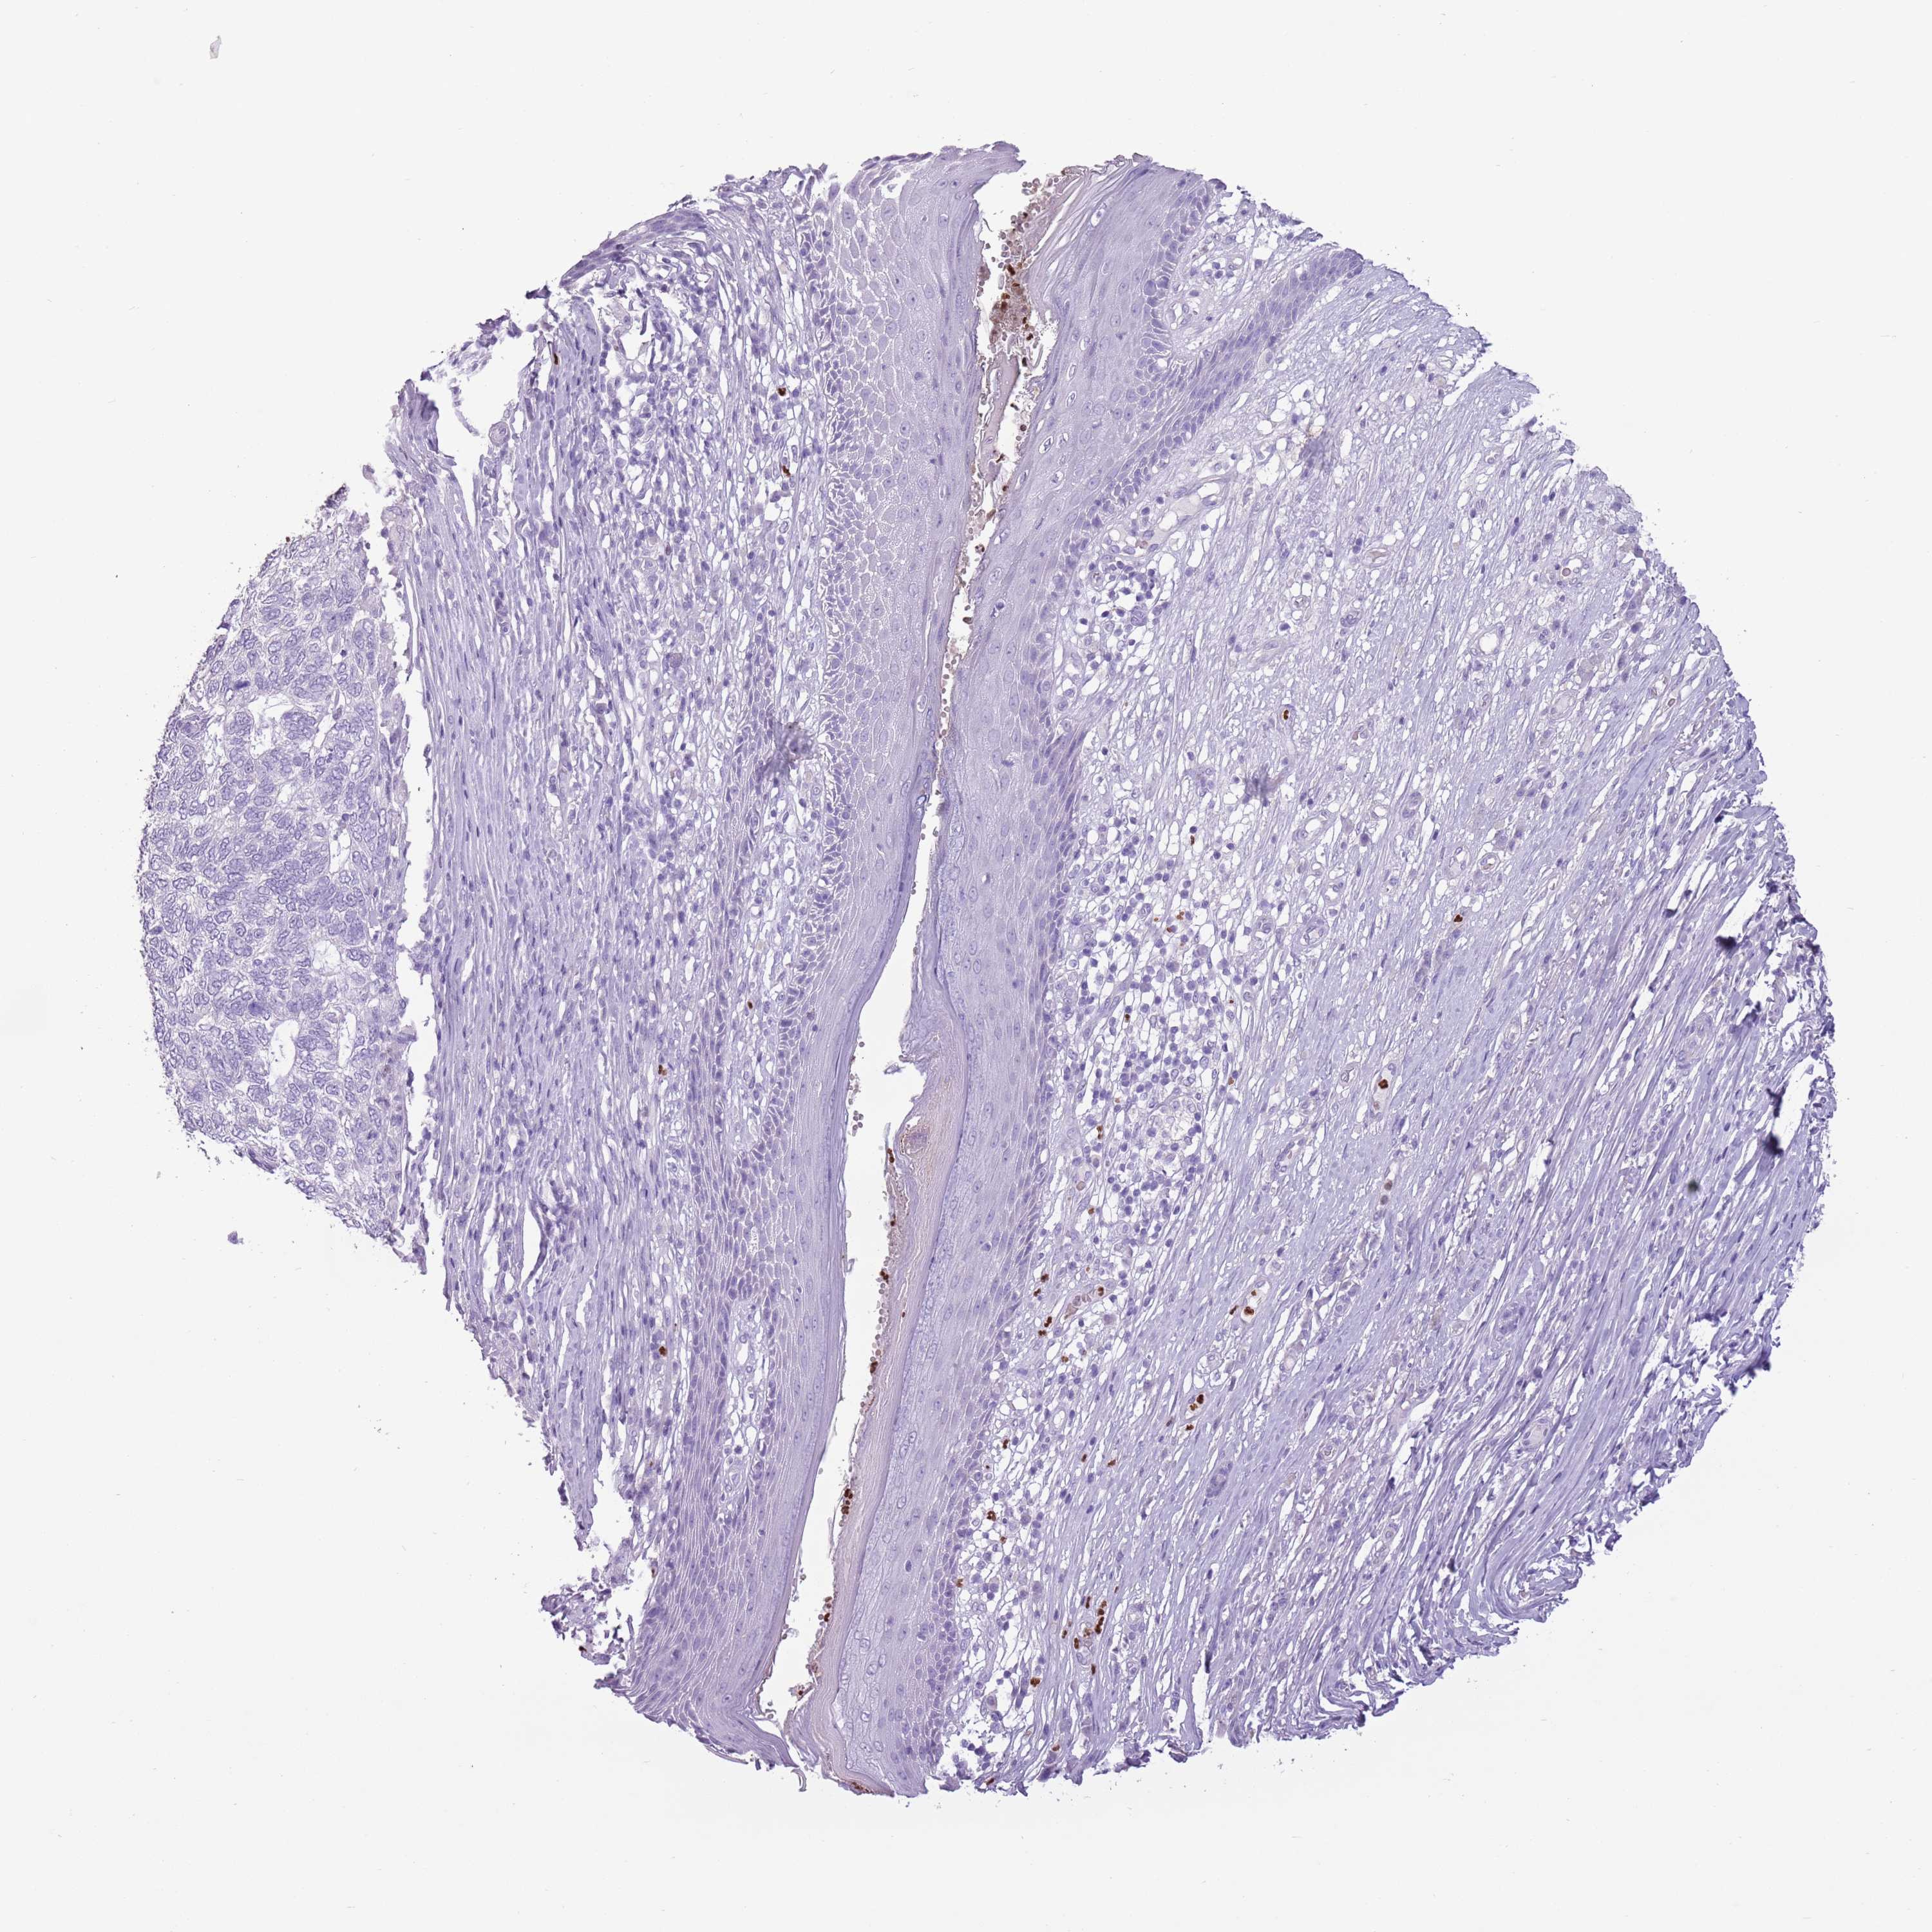

CANCER SKIN CANCER Show tissue menu

Basal cell and squamous cell cancer

SKIN CANCER - Protein expressioni

A mouse-over function shows sample information and annotation data. Click on an image to view it in a full screen mode. Samples can be filtered based on level of antibody staining by selecting one or several of the following categories: high, medium, low and not detected. The assay and annotation is described here.

Each image is clickable and will lead to virtual microscopy that enables deeper exploration of all samples and also displays staining intensity scores, fraction scores and subcellular localization as well as patient and tissue information for each sample.

Antibody HPA046985

Antibody HPA053526

Basal cell carcinoma

Squamous cell carcinoma, NOS

Squamous cell carcinoma, metastatic, NOS